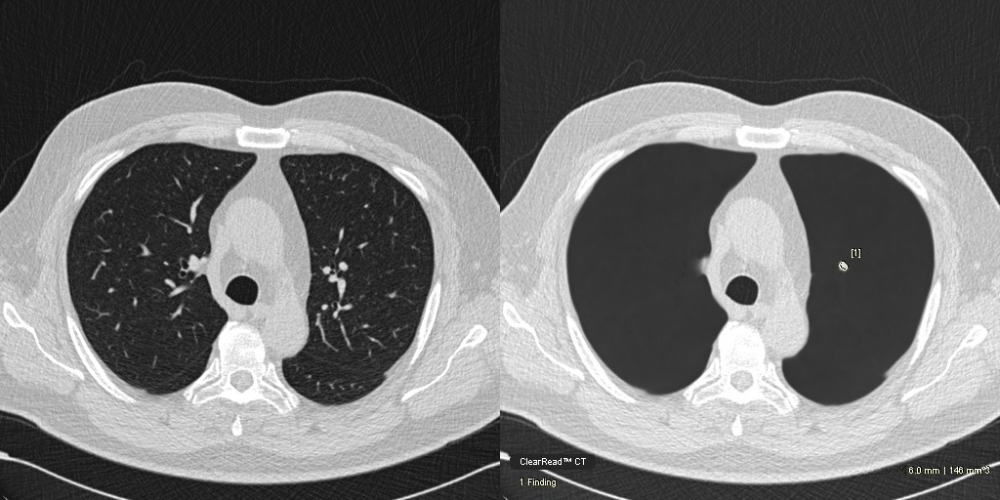

Vessel Suppression An unimpaired view for enhanced confidence in findings

- Exclusive vessel suppression capability provides an unimpaired view of the chest and is approved for concurrent reading